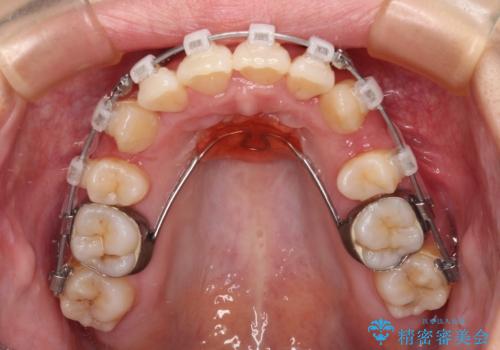

- クリアブラケット

- 1年11ヶ月

八重歯をスムーズに解消するために、補助装置を用いることで速やかに歯列を整えることができました。